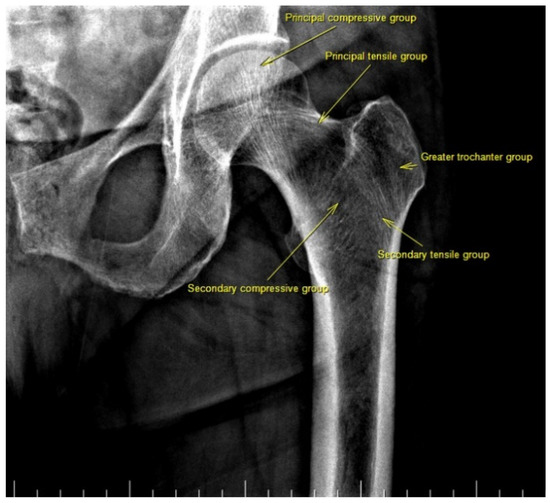

Last week I had a bone density scan. They took pictures of my lower back, left hip and left arm. Today I got the results and...